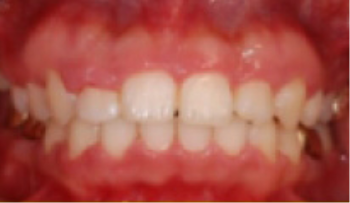

• 총생(Crowding) 치아가 삐뚤게 남.

Before

After